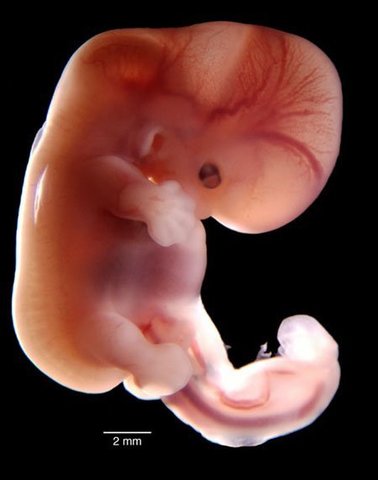

• Semana 3: Disco embrionario trilaminar

Semana 3: Disco embrionario trilaminar

La forma del embrión sigue como disco ovalado y ha alcanzado a medir 2 mm. Posee ahora tres hojas de tejido.